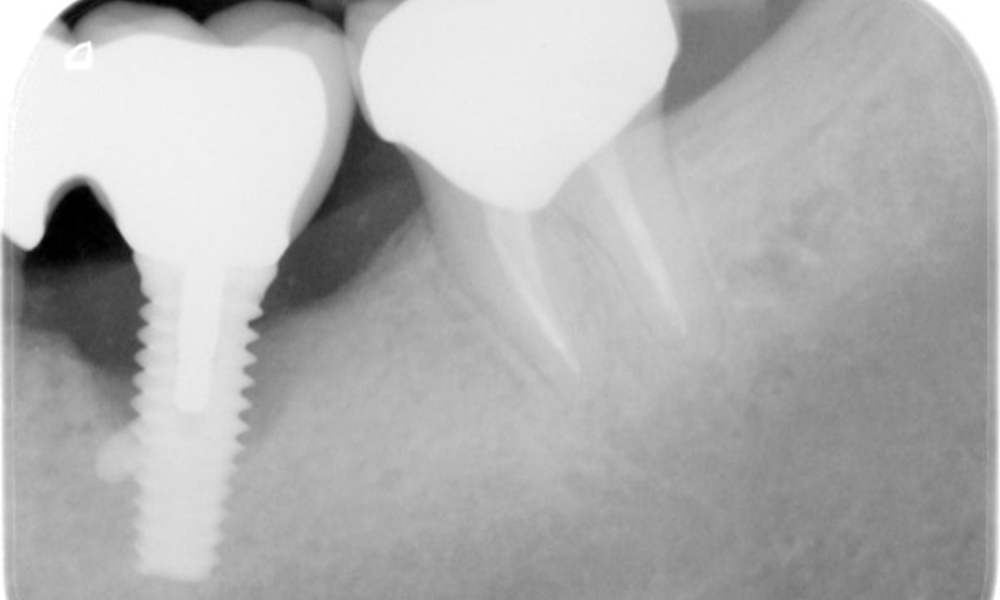

The X-ray images show the progression of bone loss in the area of the implant in region 36: dental film from 11.02.2021 (left) and dental film from 18.01.2024 (right).